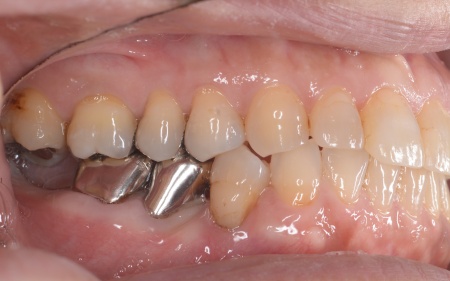

| カウンセリング | 拝見したところ、右下奥歯2本が噛むと痛む状態でした。 これらの歯は、以前神経を除去する処置を行っており、その後銀歯にされていたとのことです。 詳しく調べるためにレントゲン撮影を行った結果、どちらの歯も歯根が割れていることが確認できました。 歯根が割れた歯は元の状態に戻すことができず、そのまま放置すると炎症が広がって周囲の骨や隣接する歯に悪影響を及ぼすリスクがあります。 以上のことから、抜歯をしたうえで歯を補う治療が必要だと診断しました。 |